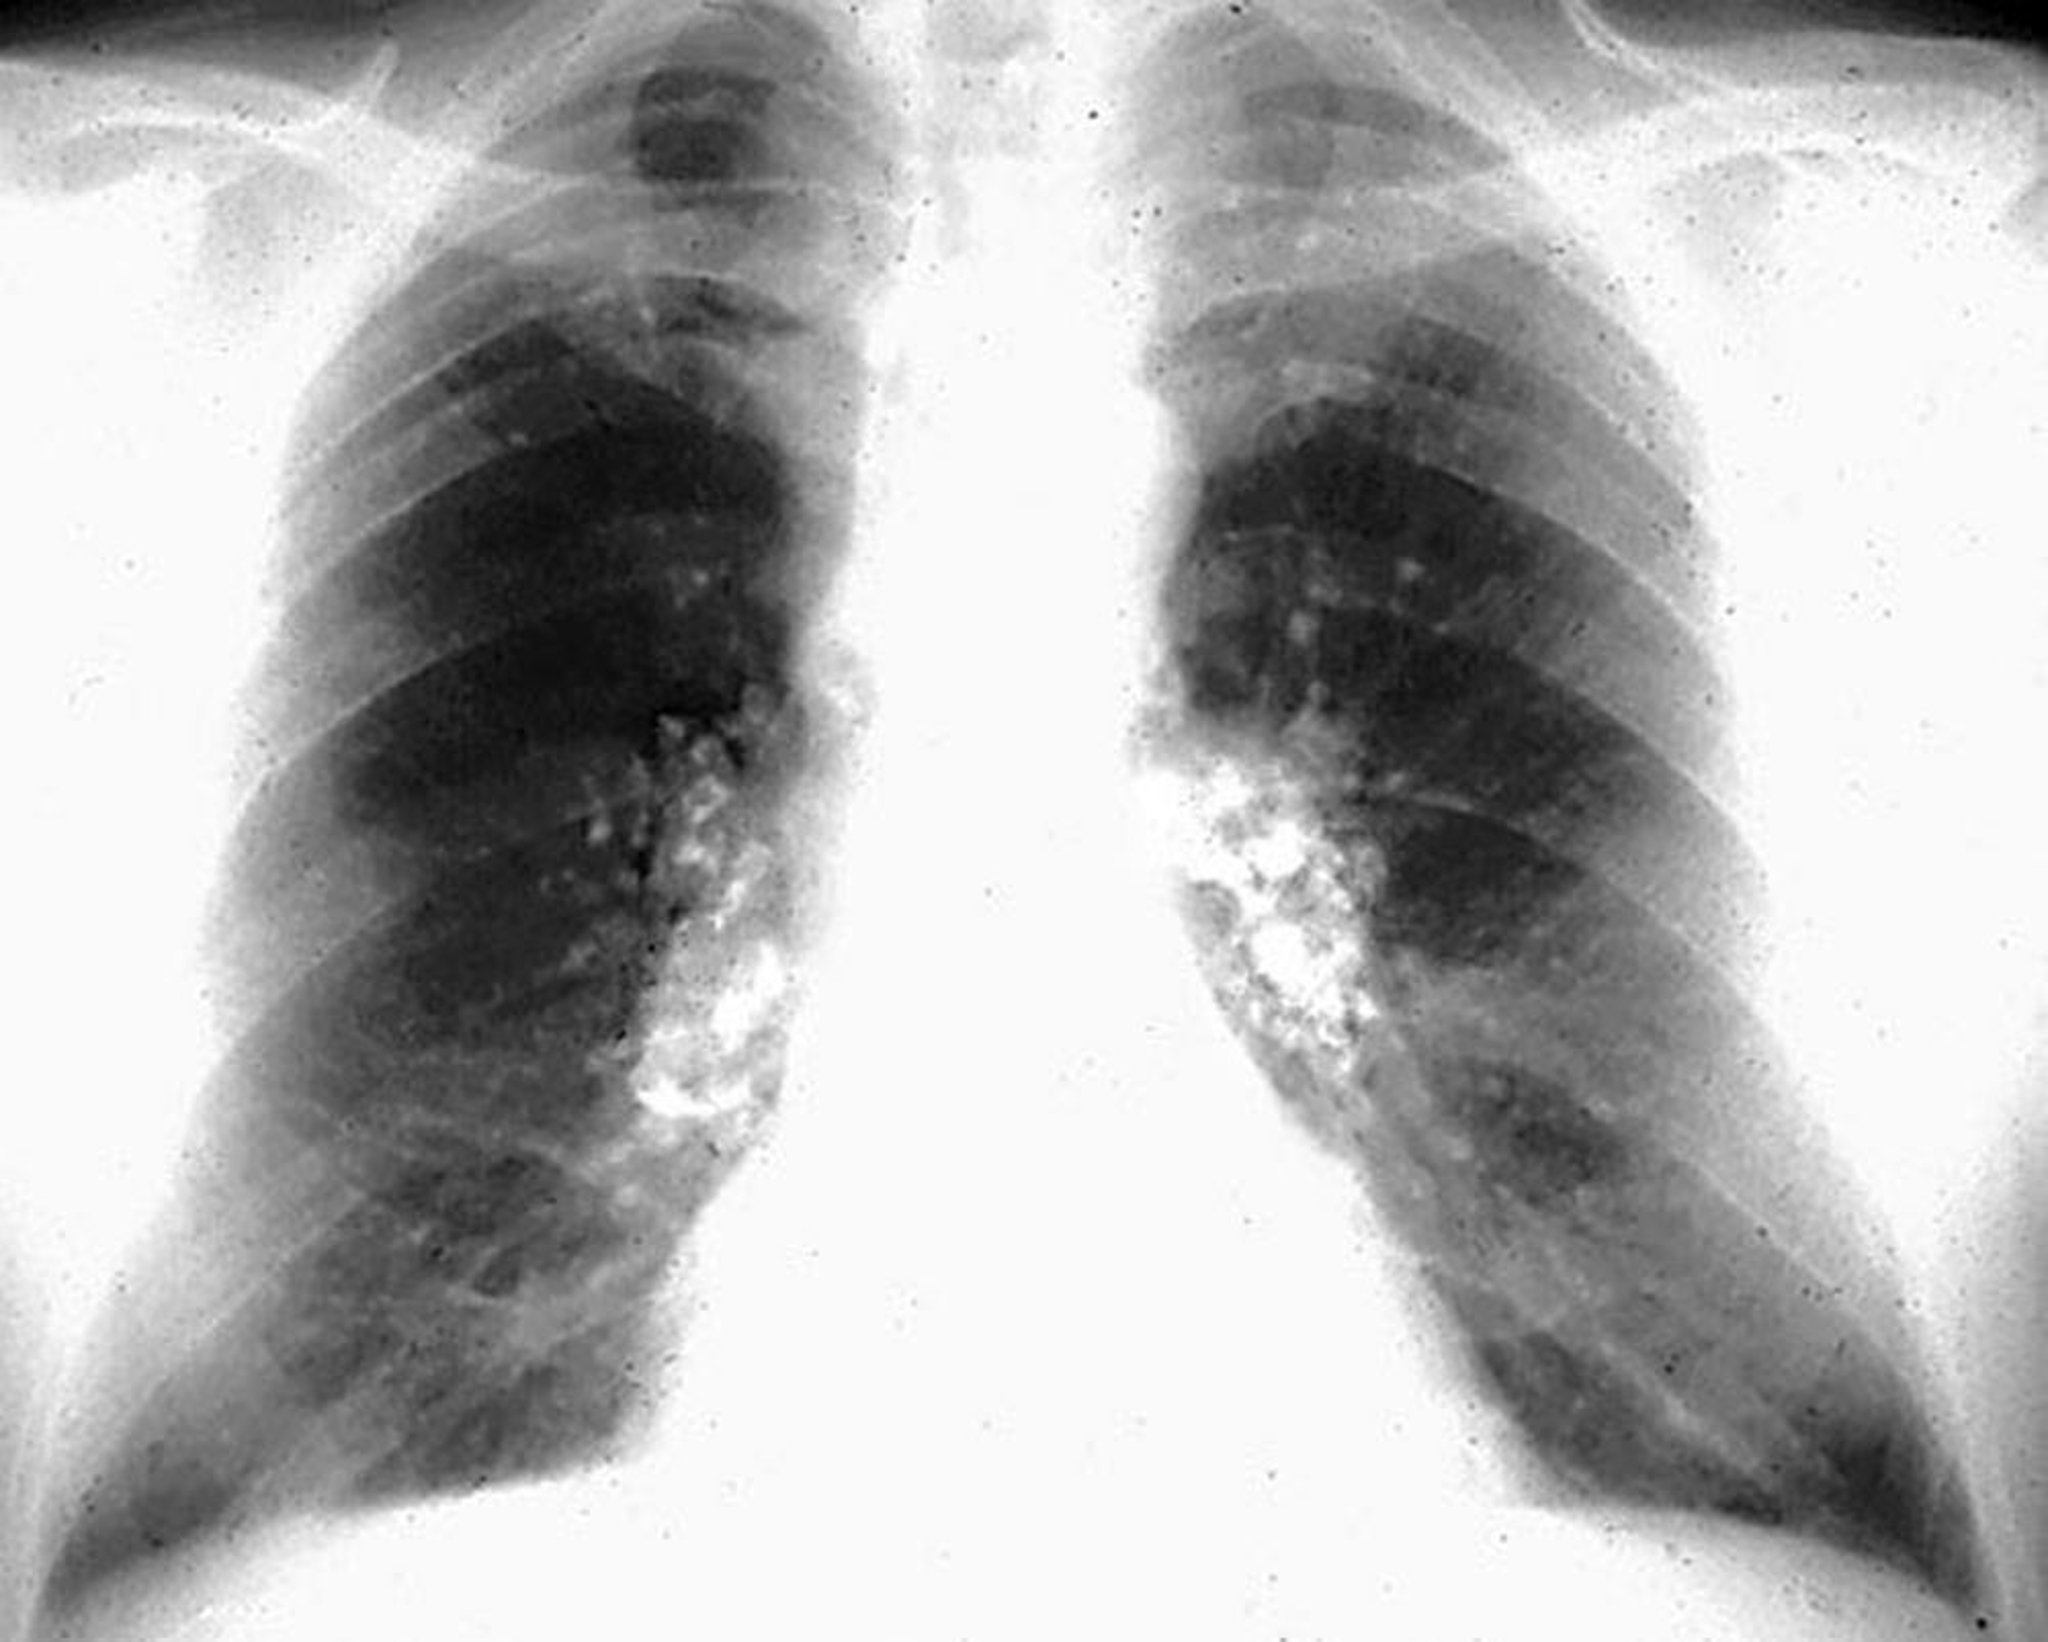

Silicosi, calcificazioni a guscio d'uovo

Image courtesy of David W. Cugell, MD.